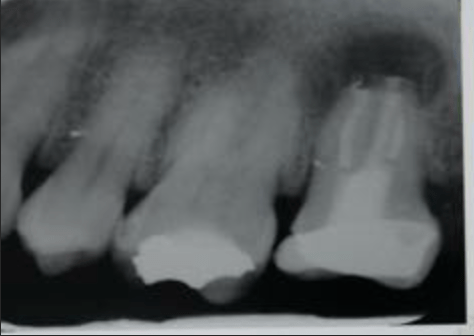

Fisura, remoción amalgama para explorar

Fractura cuspídea tratable

Vertical root fracture